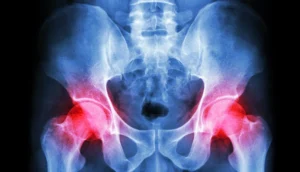

درد مداوم لگن یا ساییدگی مفصل ران میتونه زندگی روزمره رو حسابی سخت کنه، بهخصوص برای افراد میانسال یا مسنتر. وقتی هر دو مفصل لگن آسیب جدی دیده باشن، تعویض مفصل تنها راه حل برای برگشتن به یه زندگی بدون درد و فعاله.

معمولاً این جراحیها بهصورت جداگونه انجام میشن: یه مفصل امروز، اون یکی چند ماه بعد. اما یه روش جدید به اسم جراحی دو طرفه لگن وجود داره که هر دو مفصل رو توی یه عمل تعویض میکنن. این روش نیاز به مهارت و تجربه خیلی زیادی داره و تو ایران، دکتر بهرام نقیبی یکی از بهترینهاست که این جراحی رو با استانداردهای جهانی انجام میده.

توی این روش، جراح تو یه جلسه هر دو مفصل ران آسیبدیده رو با مفصل مصنوعی جایگزین میکنه. این جراحی برای کسایی مناسبه که هر دو طرف لگنشون به یه اندازه مشکل داره و دنبال راهحلی سریعترن.